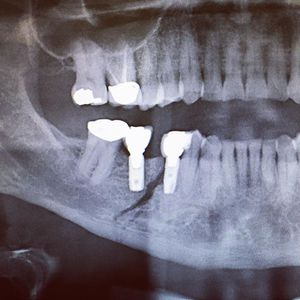

What happens when the jaw breaks exactly between two implants? ..... You fix it! Part 2 coming soon 👌